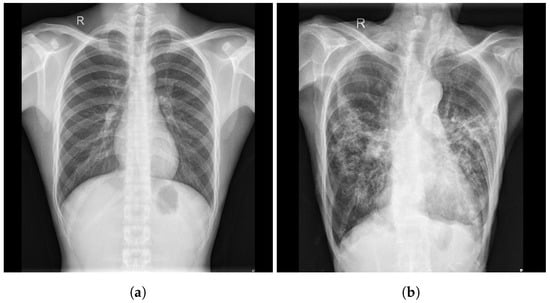

2. Proposed Approach

3. Datasets